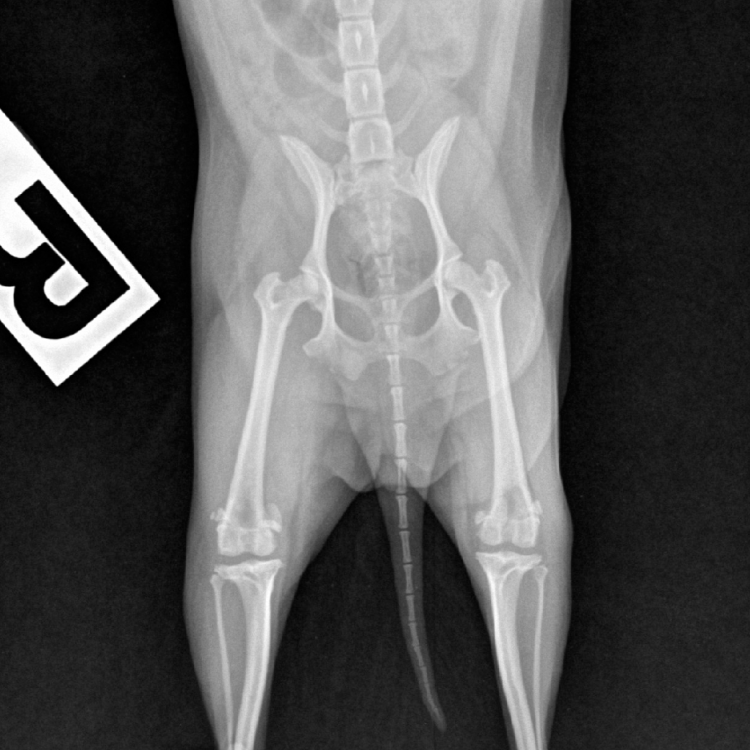

การตรวจเอกซ์เรย์ (X-Ray) เป็นการตรวจวินิจฉัยด้วยรังสี x โดยภาพที่ได้จะมีสีขาว - ดำ

ที่มีระดับความเข้มของสีที่แตกต่างกันขึ้นกับการดูดกลืนรังสีของแต่ละอวัยวะ

ตำแหน่งในการเอ็กเรย์ถูกแบ่งออกเป็น 3 ระบบหลักๆ คือ

การถ่ายภาพเอกซเรย์ (X-ray) ให้กับสัตว์ป่วย โดยทั่วไปไม่จำเป็นต้องเตรียมตัวพิเศษนัก ยกเว้นในบางกรณี เช่น การถ่ายภาพเอกซเรย์ข้อสะโพกที่สัตว์อาจเกิดความเจ็บปวด